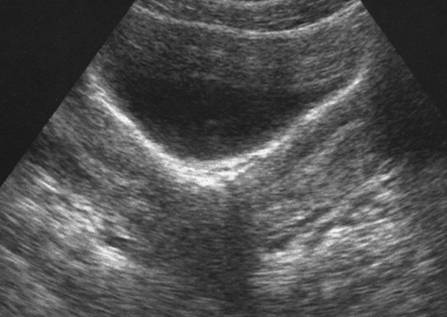

Utérus bicorne. Voie abdominale ( Cliché : Dr. M. YVINEC)